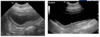

•How many layers are visible in an U/S image of a normal bladder wall? What are they?

What does this show?

Left – large soft tissue structure. Non contrast; non filtering enlarged L kidney

R – some contrast in ureter and leaving renal pelvis